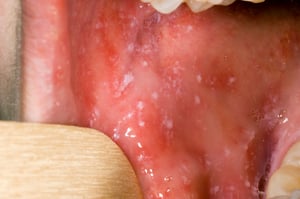

दाने शुरू होने से पहले, कॉप्लिक स्पॉट्स मुंह के अंदर दिखाई दे सकते हैं। कॉप्लिक स्पॉट्स सफेद या नीले सफ़ेद केंद्रों वाले चटकीले लाल धब्बे होते हैं। हो सकता है कि ये दाग रेत के दानों के समान दिखाई दें।

कॉप्लिक स्पॉट्स सफेद या नीले सफ़ेद केंद्रों वाले चटकीले लाल स्पॉट्स होते हैं, जो हो सकता है कि रेत के दानों के समान हों। खसरे से पीड़ित लोगों के मुंह में हो सकता है कि ये कहीं भी हों।

चित्र, रोग नियंत्रण और रोकथाम केंद्रों की पब्लिक हेल्थ इमेज लाइब्रेरी के सौजन्य से।